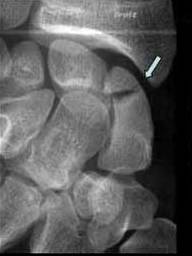

FRACTURA DE SCAFOID

Intreruperea corticalei cu artefact subiacent →

Ligamentul scapulo lunar este continuu

Confirmare radiografica